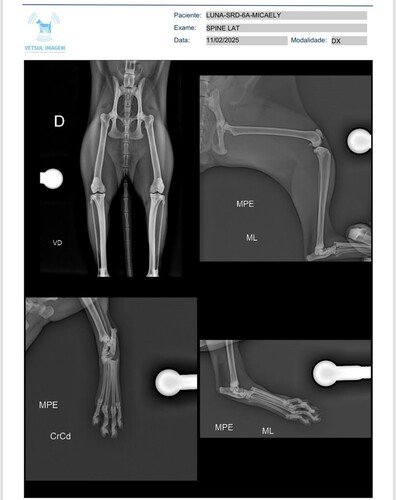

Não sabemos ao certo como aconteceu, mas os exames mostraram que ela teve perda total da relação articular entre os ossos do tarso e metatarsos, o que compromete muito sua mobilidade.

Até agora, já gastamos R$ 550,00 com raio-x, sedação e imobilização da patinha, e estamos arrecadando esse valor para cobrir os custos do atendimento veterinário.